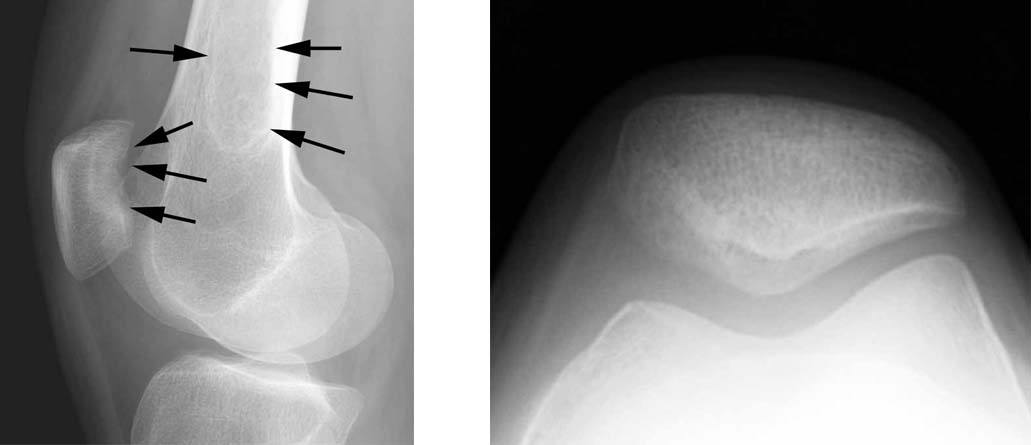

The patient is a 40 year old male with a work related injury to his knee when lifting a 90 lbs suitcase. He had complaints of pain on the inside (medial aspect) of his knee.

1.The standard radiographs of his knee shows an irregularity of the medial femoral condyle (black arrows).

2.This sagittal MRI image shows irregularity of the articular cartilage surfaces in the medial femoral condyle and medial tibial plateau (small white arrows). There is also bone edema (black arrow) noted in the femoral condyle consistent with early degenerative changes. The posterior horn of the medial meniscus appears normal (white arrowhead).